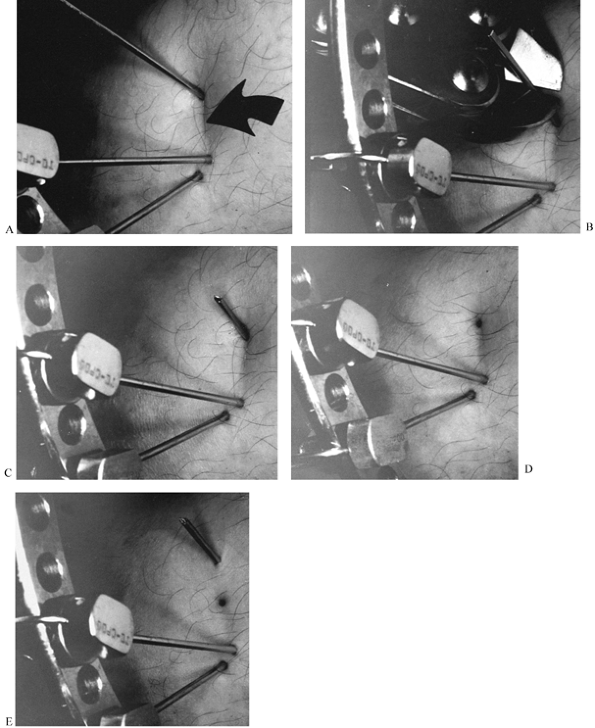

![]() |

Figure 32.38. If one adds rotation to the evaluation of angular deformity, then an xyz

graph can be used to determine the orientation of the axis and magnitude of the deformity. The oblique plane deformity is calculated first in the method described. One then plots the oblique plane magnitude on the x axis and the rotational magnitude on the z or axial axis. In the example illustrated, there is a 25° varus angulation and a 25° procurvatum angulation, producing a 35° oblique plane deformity oriented 45° to the frontal plane. In addition, there is a 34° rotational deformity. This is plotted on the axial axis. The graph demonstrates a 39° angular deformity oriented at a 44.5° inclination to the transverse plane. This axis can be further qualified as oriented at 45° to the frontal plane on the transverse cut. |

either through a single hinge or sequentially. The correction requires

vertical plane. This vertical inclined hinge will simultaneously

correct the angular and rotational deformities (Fig. 32.39).

Figure 32.39. A:

Vertical inclined plane hinge. When the paper is folded with the tibia marked on it along a vertical oblique axis, the tibial diaphysis is both realigned as to its angular deformation and derotated. B: This principle can be applied to the Ilizarov apparatus. By using universal hinges, two rings can be connected by hinges at different levels. The axis of rotation is no longer parallel to the plane of the rings but rather is in a plane that is vertically oblique to the rings. C: In this simulation, the upper ring can be seen to pivot through the vertical oblique axis. Notice the position of the central bolt connecting the half rings on the moving ring relative to the central bolt on the stationary ring. In this reduced position, the central bolts are properly aligned. In the flexed position, the central bolts are rotated with respect to each other. |